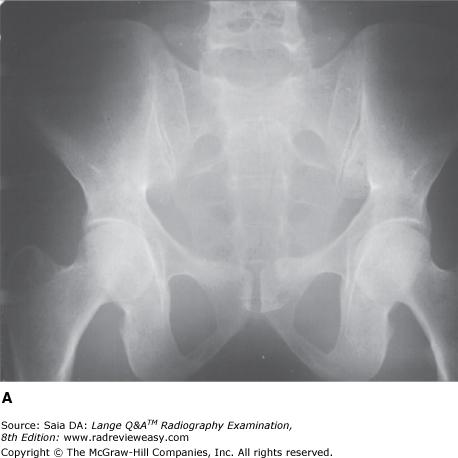

Which of the following statements is (are) true regarding the images below?

- Image A was made using a higher kilovoltage than image B.

- Image A was made with a higher-ratio grid than image B.

- Image A demonstrates shorter-scale contrast than image B.

A 1 only

B 1 and 2 only

C 2 and 3 only

D 1, 2, and 3

-Image A was made using 80 kV at 75 mAs; image B was made using 100 kV at 18 mAs; all other exposure factors remained the same. As kilovoltage is increased, the percentage of scattered radiation relative to primary radiation increases—hence, the grayer appearance of image B. Use of optimal kilovoltage for each anatomic part is helpful in keeping scatter to a minimum. The production of scattered radiation also will be limited if the field size is as small as possible. A grid is the most effective way to remove scattered photons from those exiting the patient. Grids are designed to selectively absorb scattered radiation while absorbing as little of the useful beam as possible. Images produced with higher-ratio grids are likely to evidence the effect of less scattered radiation than those made with lower-ratio grids.

The radiograph of the pelvis shown in the figure below is unacceptable because of

A motion.

B inadequate penetration.

C scattered radiation fog.

D double exposure.

-Radiographic contrast, especially in analog images, can be greatly affected by changes in kilovoltage (see figures below). As kilovoltage increases, a greater number of high-energy photons are produced at the target. These photons are more penetrating, but they also produce more scattered radiation, contributing to lower radiographic contrast as a result of scattered radiation fog. Radiograph B was made using 100 kVp and 18 mAs. Radiograph A was made of the same part using 80 kVp and 75 mAs, all other factors constant. The image details in radiograph A are far more perceptible as a result of the production of less scattered radiation